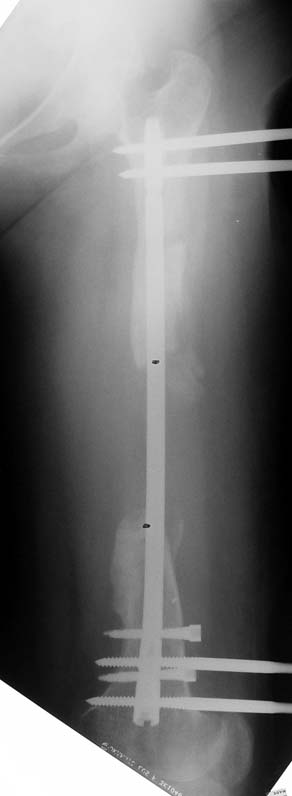

Bu Bacak Kısalık tipi bir kırığın kısalmış pozisyonda kaynaması ile oluşur. Bir çok vaka yetişkinlerde görülür ve sadece bir uzatma ile tedavi edilebilir. Ek deformiteler de aynı anda düzeltilebilir. Bu hastaların çoğu çivi üzerinden uzatma veya tam implante edilen çivi ile tedavi edilebilirler.